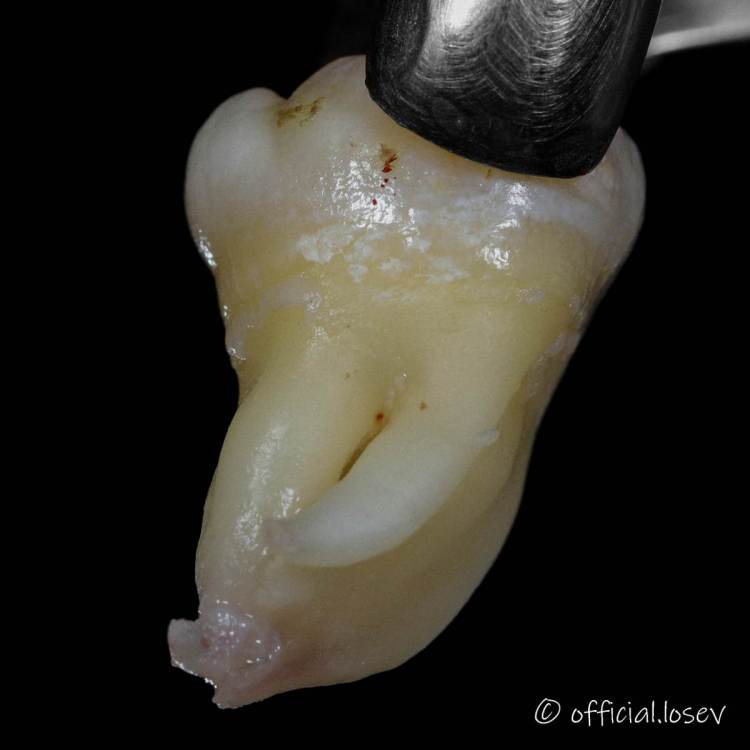

It'sGeorgy Опубликовано 12 марта, 2021 Поделиться Опубликовано 12 марта, 2021 Сегодня был Кинг-сайз: 4 Ссылка на комментарий

Raystom Опубликовано 12 марта, 2021 Поделиться Опубликовано 12 марта, 2021 Сегодня был Кинг-сайз:77ACA2FA-C768-41BD-A47A-7FB9E5267020.pngCBA9ECB9-7FF0-400F-9532-0BD5DA33C825.jpeg78D8DF61-36CB-4F3C-BD57-D07106E56D33.jpegПочти как корона из бургер-кинга) Ссылка на комментарий

vse32 Опубликовано 12 марта, 2021 Поделиться Опубликовано 12 марта, 2021 Сегодня был Кинг-сайз:77ACA2FA-C768-41BD-A47A-7FB9E5267020.pngCBA9ECB9-7FF0-400F-9532-0BD5DA33C825.jpeg78D8DF61-36CB-4F3C-BD57-D07106E56D33.jpegКрасавцы все. И зуб и доктор! Ссылка на комментарий

Женька Опубликовано 12 марта, 2021 Поделиться Опубликовано 12 марта, 2021 Сегодня был Кинг-сайз:77ACA2FA-C768-41BD-A47A-7FB9E5267020.pngCBA9ECB9-7FF0-400F-9532-0BD5DA33C825.jpeg78D8DF61-36CB-4F3C-BD57-D07106E56D33.jpegкак без распилов такой достали? Ссылка на комментарий

It'sGeorgy Опубликовано 12 марта, 2021 Поделиться Опубликовано 12 марта, 2021 Красавцы все. И зуб и доктор!Благодарю как без распилов такой достали? Если честно, сам не понял. Был под впечатлением от ОАС на вч размером с палец, которое получил, когда верхнего удалял. Убрал кость до уровня коронки. Вестибулярно в щель байонетный элеватор и зуб вышел. Ссылка на комментарий